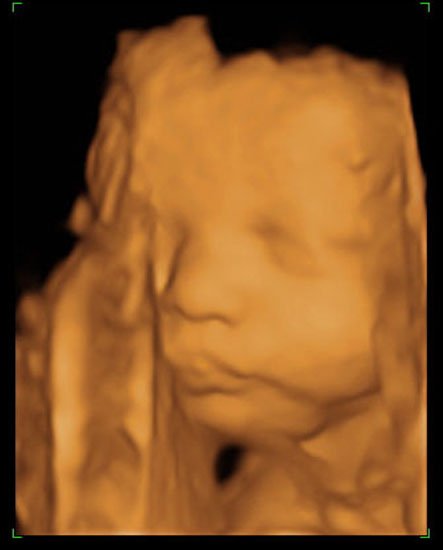

Jeg har lige været til en 3D/4D scanning (27+0), hvilket var en kæmpe oplevelse. Jeg venter en dreng på foreløbig 976 gram

Denne tråd er for alle os som har fået foretaget sådan en scanning. Jeg tænkte det kunne være sjovt at smide nogle fotos op af vores bebzere, da de lå i maven. I profil og forfra.

Skriv gerne hvilken uge scanningen er foretaget, samt evt. hvad køn det er